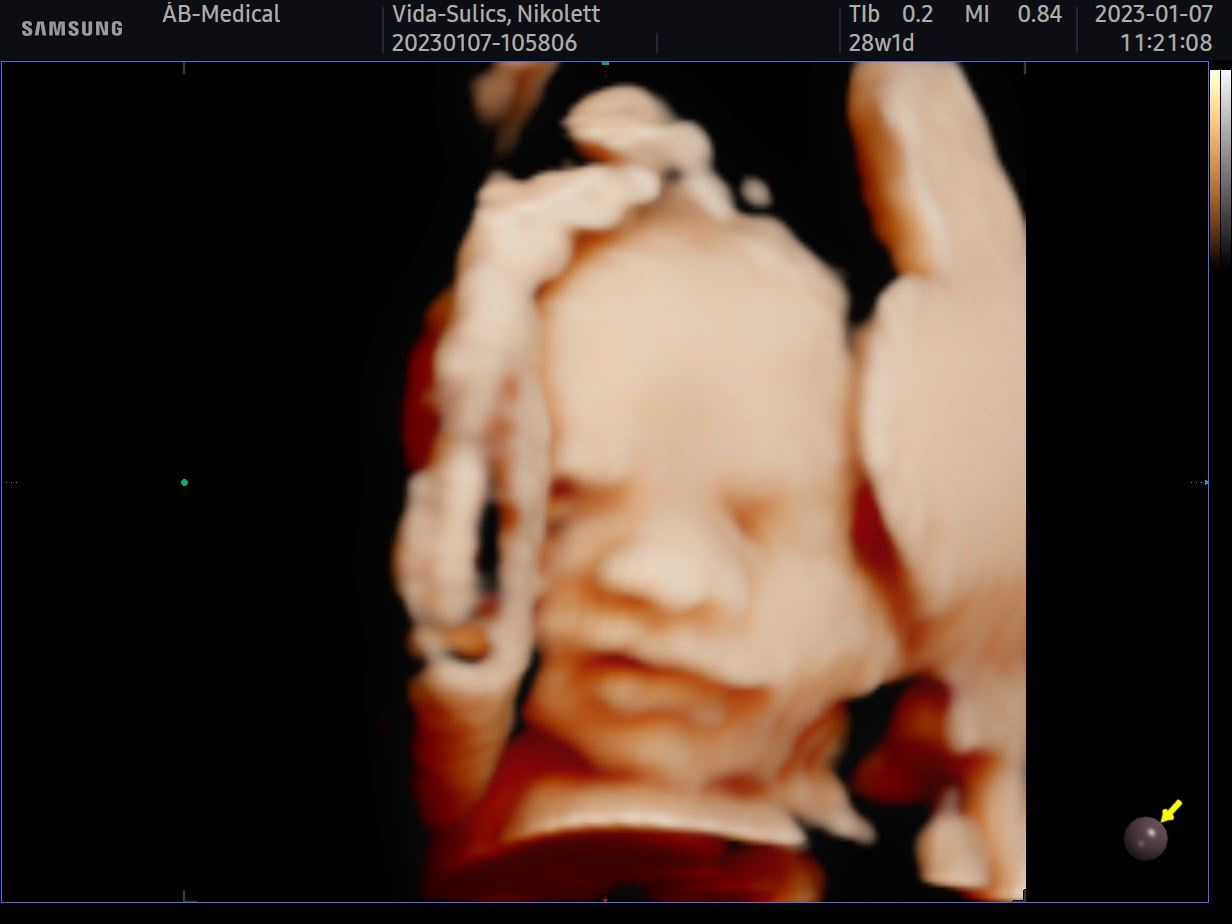

Szombaton babamozin jártunk egy nagyon kedves doktornőnél. Tavaly még teljesen felesleges pénzkidobásnak gondoltuk, így akkor nem jártunk ilyesmin. Idén elsősorban azért mentünk el, hogy legalább így láthassuk a babánkat, mert az előző kisfiunkat egyáltalán nem láttuk. Hatalmas élmény volt, legszívesebben minden nap elmennék és órákig nézegetném, hogy mit csinál odabent.

Ha még te is gondolkozol rajta, hát ne tedd, foglalj időpontot mihamarabb! Azóta is teljes extázisban vagyok és nem győzök betelni a fotók nézegetésével! Egyszerűen hihetetlen, hogy egy igazi kis emberi lény növekszik a pocakomban. Ahogy ígértem, hoztam nektek néhány fotót is.

Hamarosan nevet is illene választanunk már ehhez az édes kis pofihoz, de most valamiért nagyon nehezen megy. Nem találjuk az igazit,